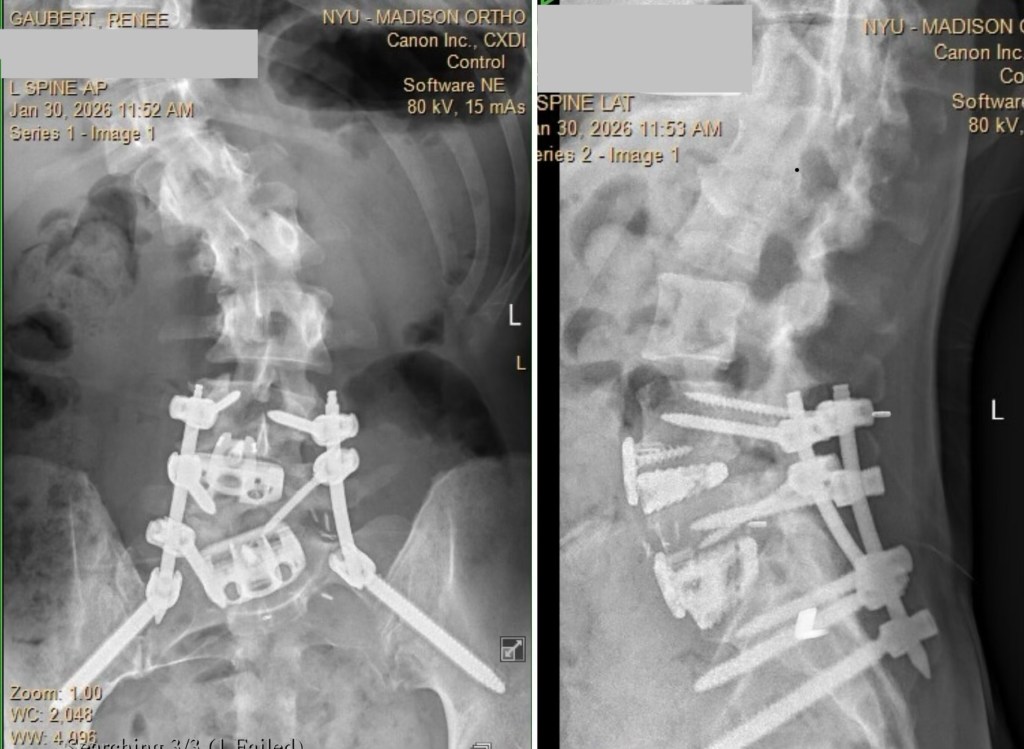

Like all trauma recovery, surgery recovery is not linear. My back pain has returned to an 8/10 the past week, which has had me pretty down. At my 6-week follow-up with my surgeon on Friday, x-rays showed my hardware’s still in place and many of my restrictions were lifted. My surgeon said my incisions have healed well and the scars look great. She said the pain in my feet is likely the nerves still adjusting to their new position. She suggested I put lidocaine patches on the tops of my feet, since that is where the burning and shooting pain is localized when I point and flex my feet. She added Tramadol as a step-down from Oxycodone, and said starting outpatient physical therapy should help reduce the pain. It doesn’t look like I’ll be able to resume working with my Schroth PT just yet, so I’ll have to find a new PT for now. I took the subway home from the appointment and was able to navigate that pretty well with my cane and bag. I’ve been able to tolerate sitting for longer periods of time, though I still find I need to lay flat on my ice pack to manage pain throughout the day. I’m cleared to use a heating pad and take baths again, so hopefully that will help, too. My hip pain is still at a 0, so I am very happy about that. My next follow-up with the surgeon will be May 1st.